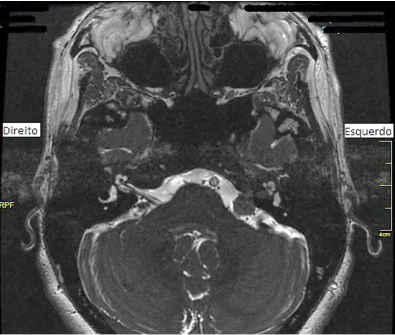

Observe a imagem a seguir e assinale a alternativa correta referente ao que ela evidencia.